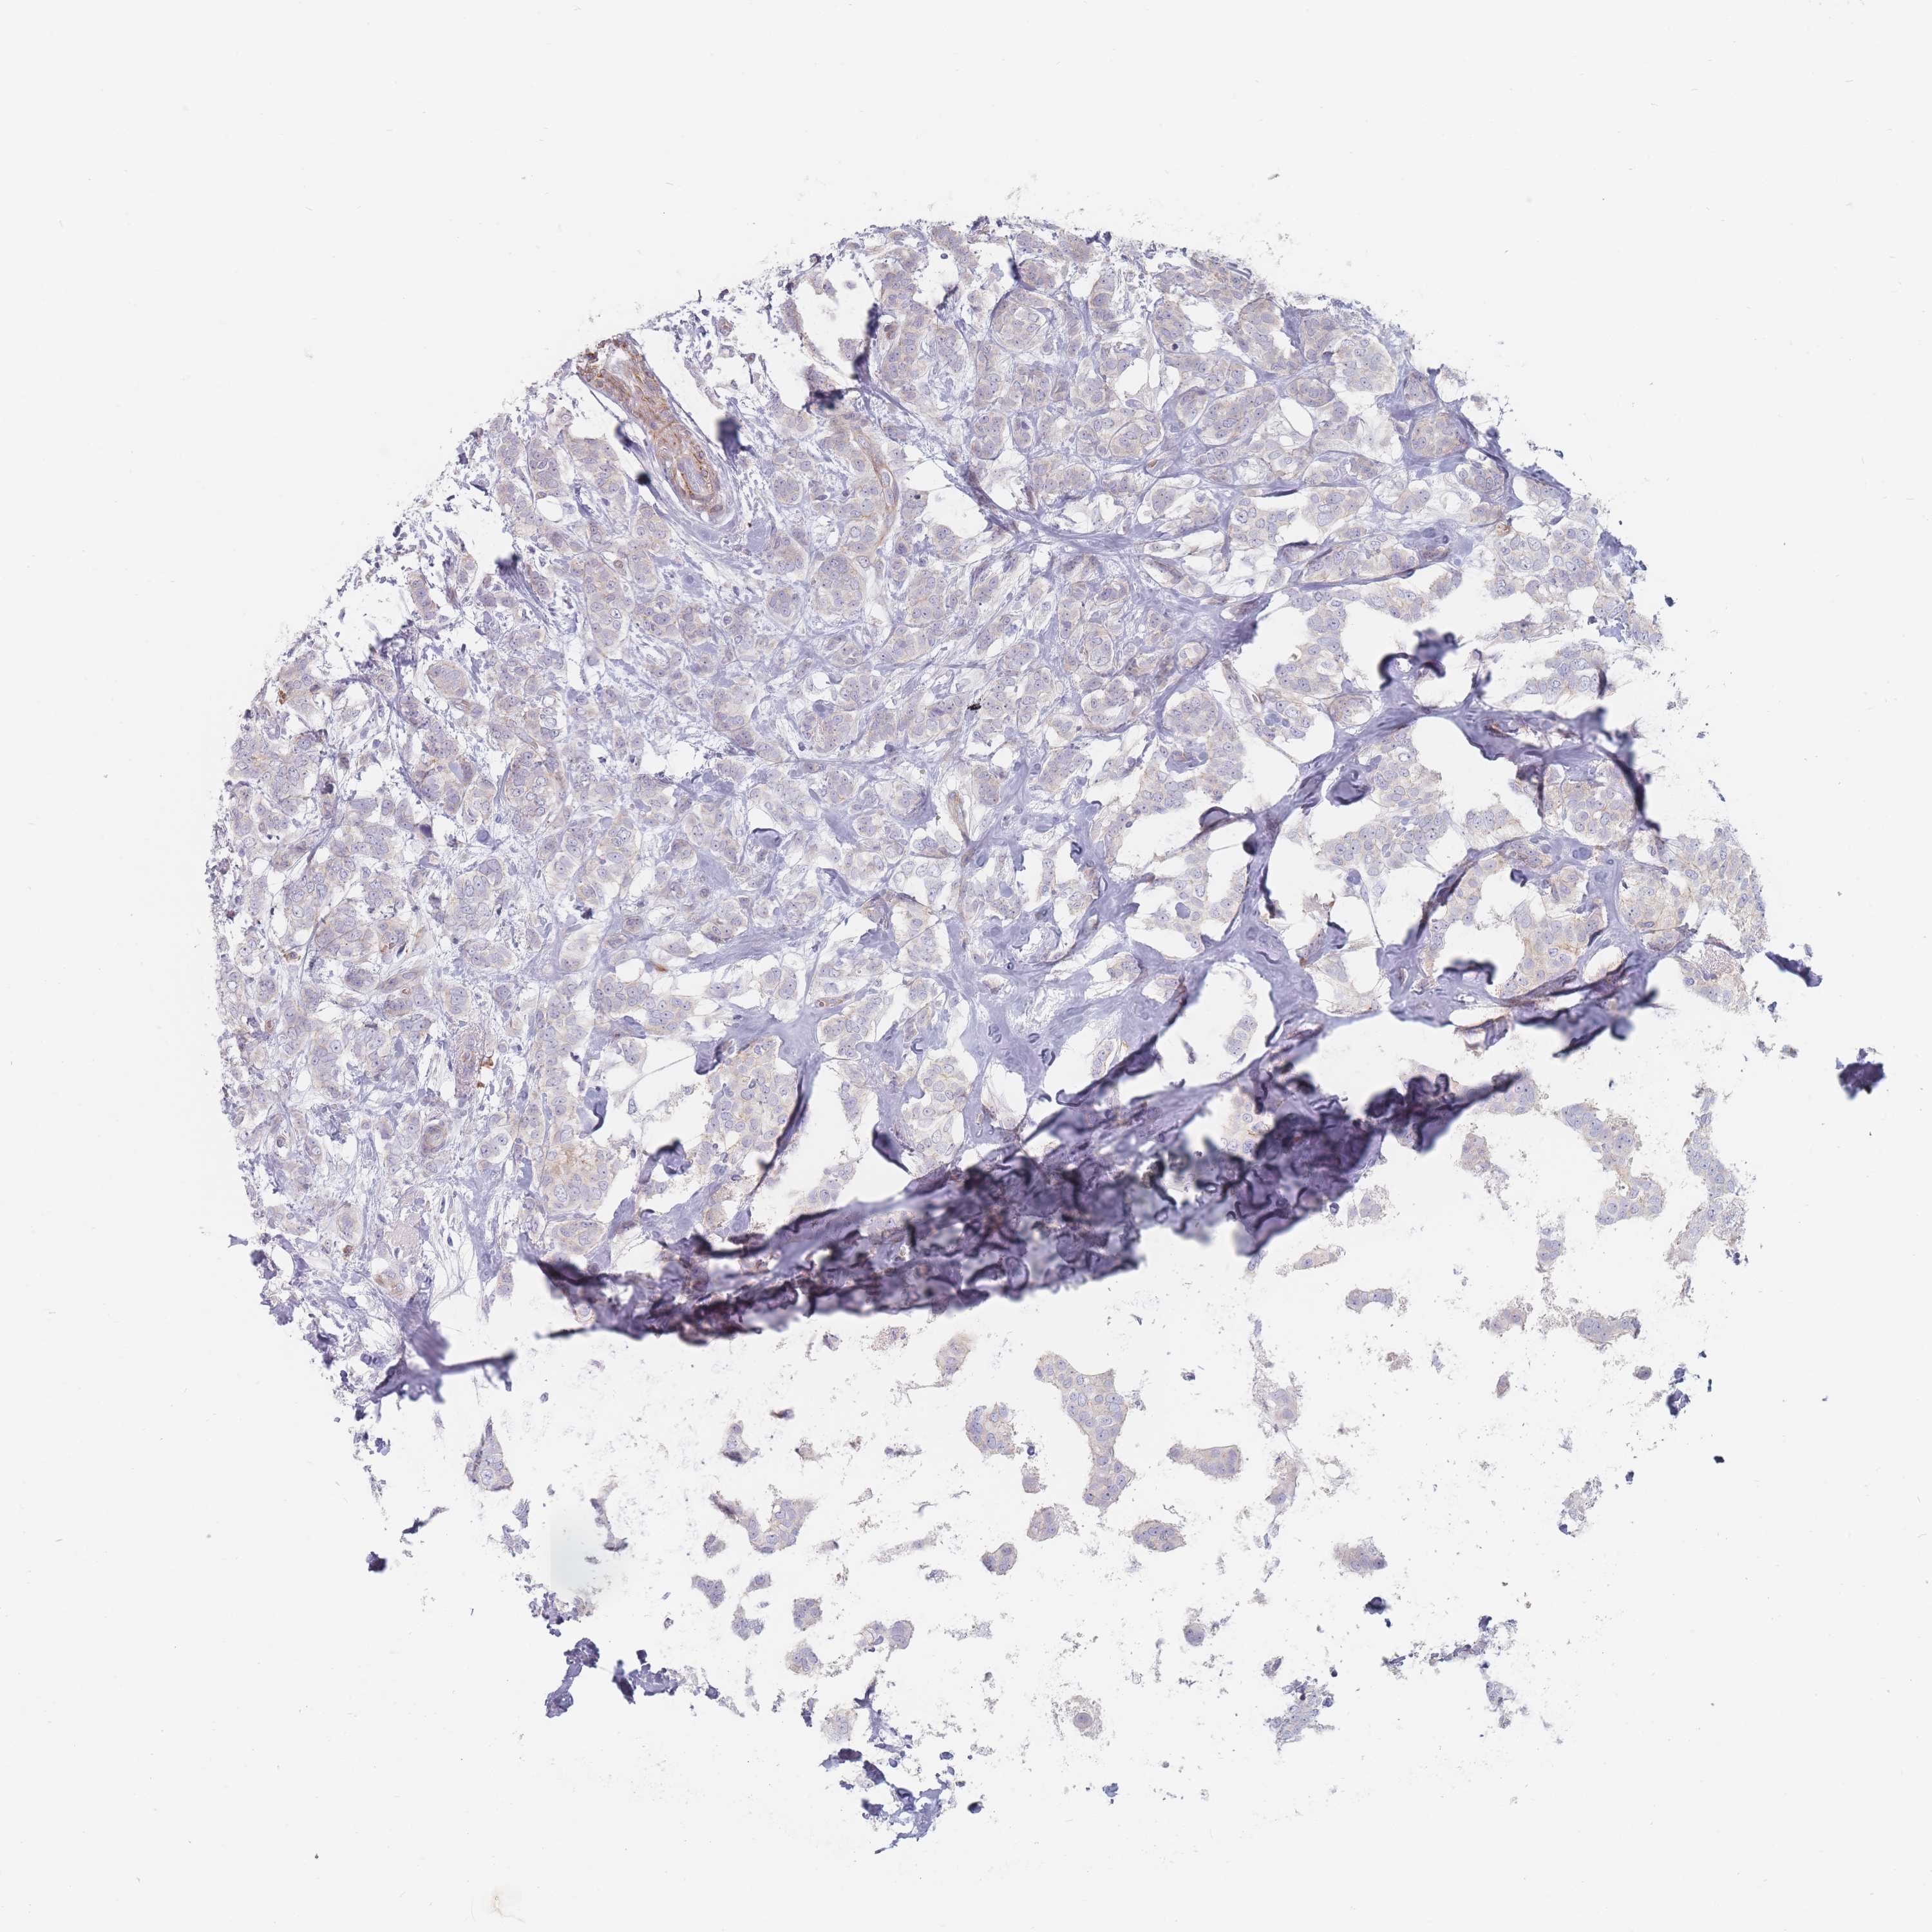

CANCER BREAST CANCER Show tissue menu

BRCA TCGA BRCA VALIDATION PROTEIN EXPRESSION